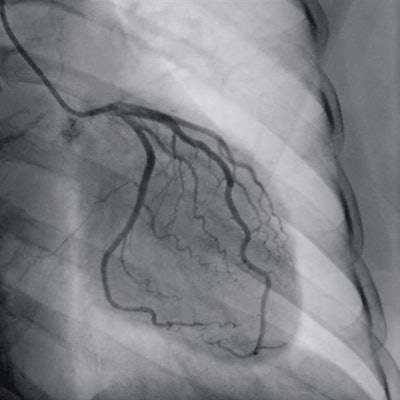

Mobile C-army developer Ziehm Imaging is showcasing its line of mini-C-arms and hybrid operating room suites. The company has long been a pioneer of mobile C-arms with flat-panel digital detectors, and most recently has been introducing C-arms using detectors based on complementary metal-oxide semiconductor (CMOS) material, such as its Ziehm Vision RFD Hybrid Edition/3D system.

Ziehm is highlighting software features and tools for different clinical applications, such as orthopedic, spine, trauma, and cardiovascular use. The company at ECR 2020 is also discussing its concept for a mobile cardiac cath lab.